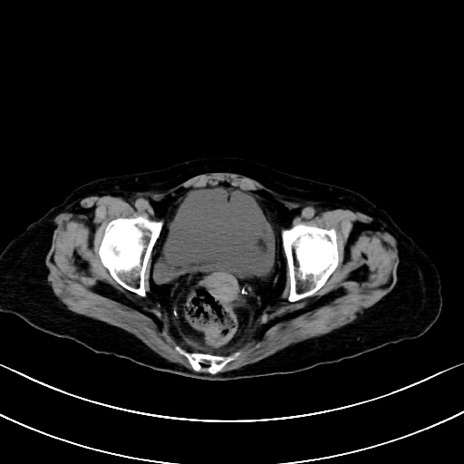

冠状断像

矢状断像